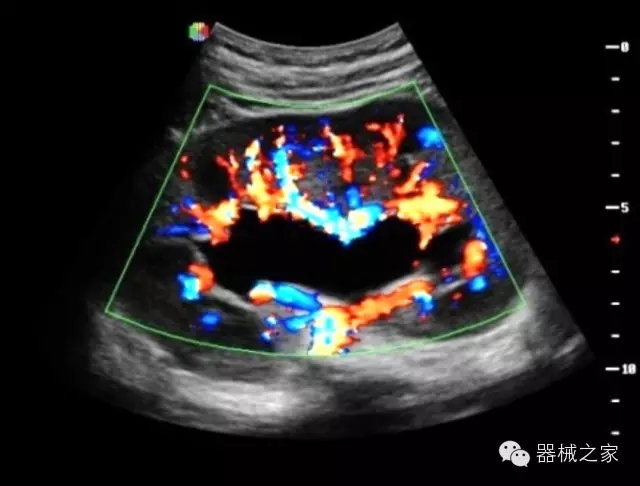

臨床圖片賞析

·亞陣元技術(shù):獨(dú)有的亞陣元技術(shù),對獨(dú)立晶片做二次切割,減少旁瓣偽像,增加臨床診斷的準(zhǔn)確性;

·μ-Scan微米成像技術(shù):開立獨(dú)有的μ-Scan技術(shù),還原出真實(shí)細(xì)膩、層次對比優(yōu)異的二維圖像;

·倒相諧波成像技術(shù):倒相諧波技術(shù)在去除基波信號的基礎(chǔ)上獲取兩倍二次諧波信號,提高組織圖像的對比分辨力;

·智能微血流成像技術(shù):智能微血流捕捉技術(shù)可以提取出隱藏在背景噪聲中的弱血流信號,大大提高低速血流的敏感性;